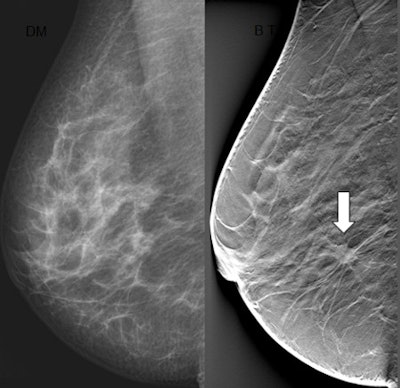

The sensitivity of mammography for detecting breast cancer is less than optimal, primarily because the breast is a 3D structure that is projected onto a 2D radiographic image. This means normal breast tissue can conceal a tumor. DBT is a 3D radiographic technique that reduces the effect of overlapping tissues in breast cancer detection.

A computer algorithm reconstructs a 3D image. The images are usually viewed as a "movie-loop" in which adjacent x-y planes are displayed sequentially. Imagers are able to see structures within the breast without overlap. The tumor is clearer, easier to see, and separate from structures in the breast.